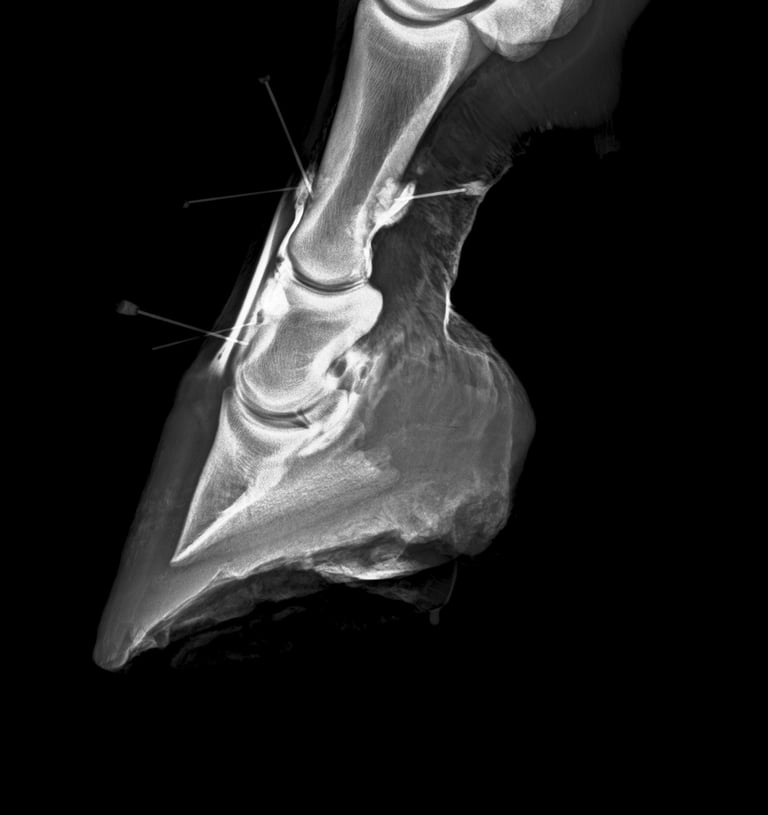

DIAGNOSTICO POR IMAGENES: ECOGRAFIA Y RADIOGRAFIA